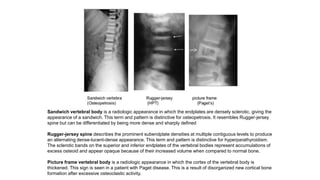

Sandwich vertebral body is a radiologic appearance in which the endplates are densely sclerotic, giving the

appearance of a sandwich. This term and pattern is distinctive for osteopetrosis. It resembles Rugger-jersey

spine but can be differentiated by being more dense and sharply defined

Rugger-jersey spine describes the prominent subendplate densities at multiple contiguous levels to produce

an alternating dense-lucent-dense appearance. This term and pattern is distinctive for hyperparathyroidism.

The sclerotic bands on the superior and inferior endplates of the vertebral bodies represent accumulations of

excess osteoid and appear opaque because of their increased volume when compared to normal bone.

Picture frame vertebral body is a radiologic appearance in which the cortex of the vertebral body is

thickened. This sign is seen in a patient with Paget disease. This is a result of disorganized new cortical bone

formation after excessive osteoclastic activity.